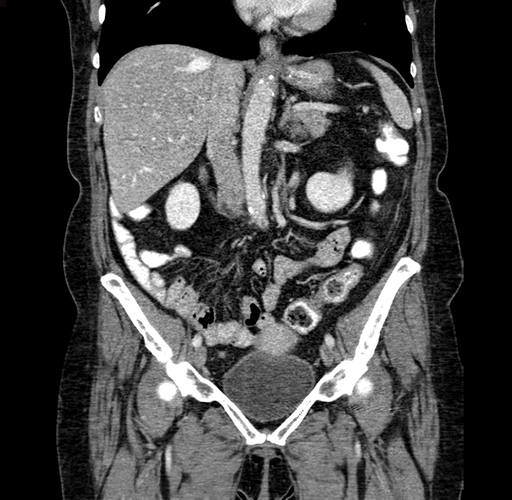

Pre-Chemo: Coronal Venous

Coronal Venous